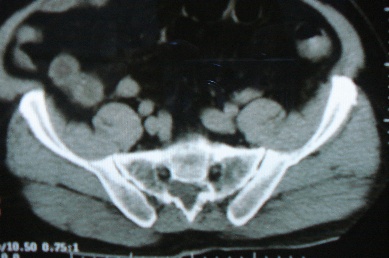

以下是引用zhangzhongshou在2007-6-17 11:53:00的发言:[br]骶管囊肿可能性大,建议mri检查。

以下是引用jinguoji在2007-6-17 14:53:00的发言:[br]骨质未见确切破坏,考虑骶管囊肿可能性大,建议mri检查。